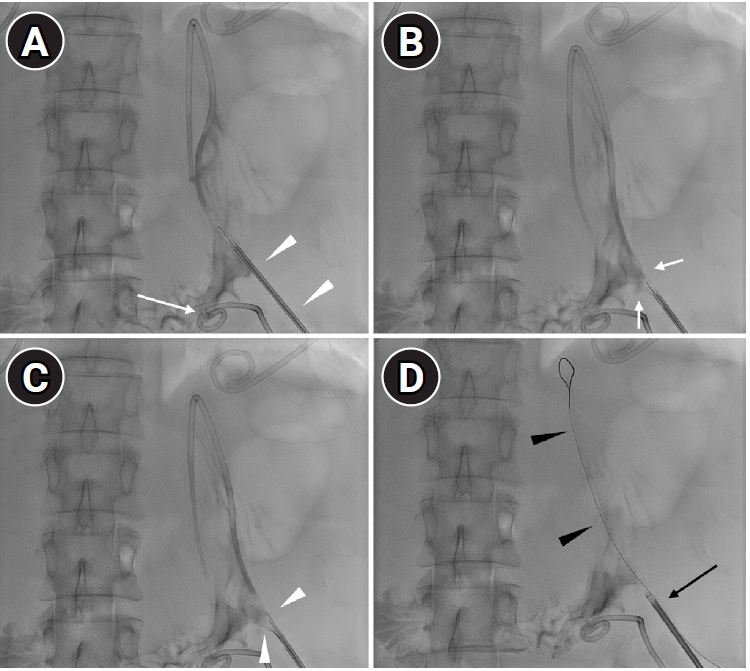

A 53-year-old woman with a history of total abdominal hysterectomy for endometrioid adenocarcinoma 2 years earlier and subsequent adjuvant chemoradiation therapy presented with adhesive ileus. She underwent adhesiolysis and small bowel resection; however, the surgery was complicated by anastomotic leakage, resulting in the formation of multifocal intraperitoneal abscesses. The perigastric abscess (

Fig. 1A) was accessed under ultrasonographic and fluoroscopic guidance. The following day, CT showed an 8.5-French PCD catheter located within the stomach (

Fig. 1B).

Fig. 1.A 53-year-old woman with a history of adhesiolysis for ileus presented with fever and abdominal pain. (A) Axial CT image shows multiloculated intraperitoneal fluid collections requiring drainage (asterisks). (B) Coronal CT image shows a percutaneous drainage catheter inadvertently placed within the stomach (arrows).